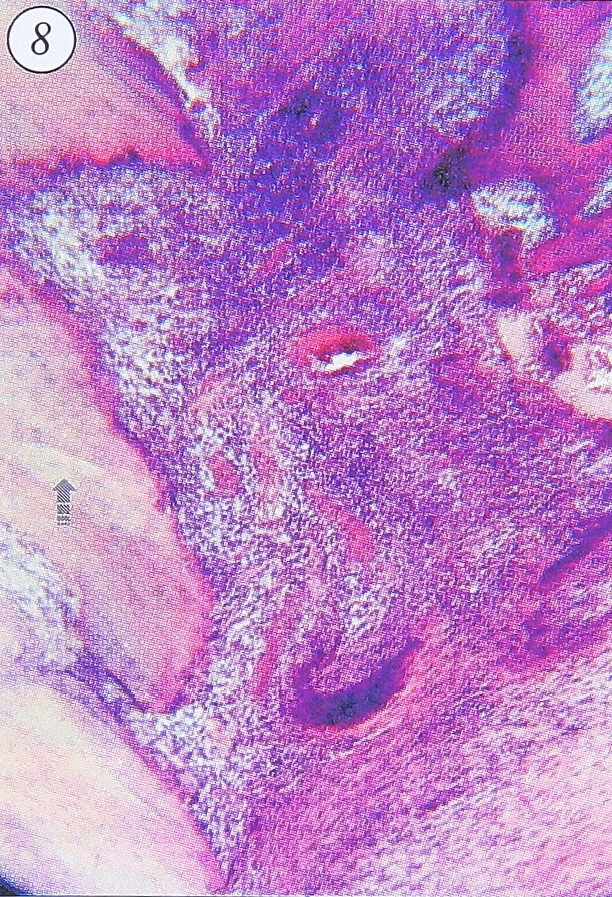

Рис. 8. Продуктивное воспаление низкой активности в фиброзной оболочке очага при хроническом травматическом остеомиелите. Неполный секвестр (стрелка). Бедренная кость больного. Ув. 60.

- продуктивное воспаление низкой активности, с немногочисленными разрозненными интерстициальными очаговыми мононуклеарно-плазмоцитарными инфильтратами (рис. 8).